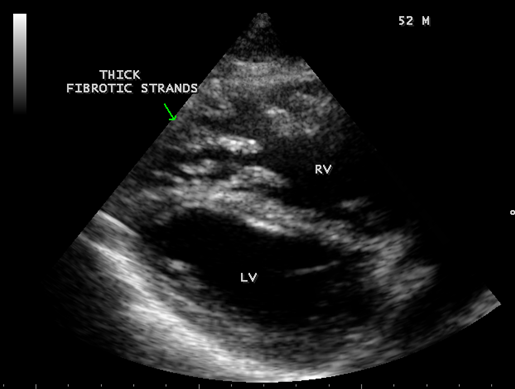

Transthoracic echocardiography revealed strong fibrous strands appearing as ‘finger like projections’ or ‘cobra-head’ appearance in the right ventricular apex due to fibrosis of muscular trabeculae, suggesting right ventricular endomyocardial fibrosis as shown in Figures 3 to 7.

Figure 7: Thick fibrotic stands in RV apex due to fibrosis of muscular trabeculae in Psoriasis.